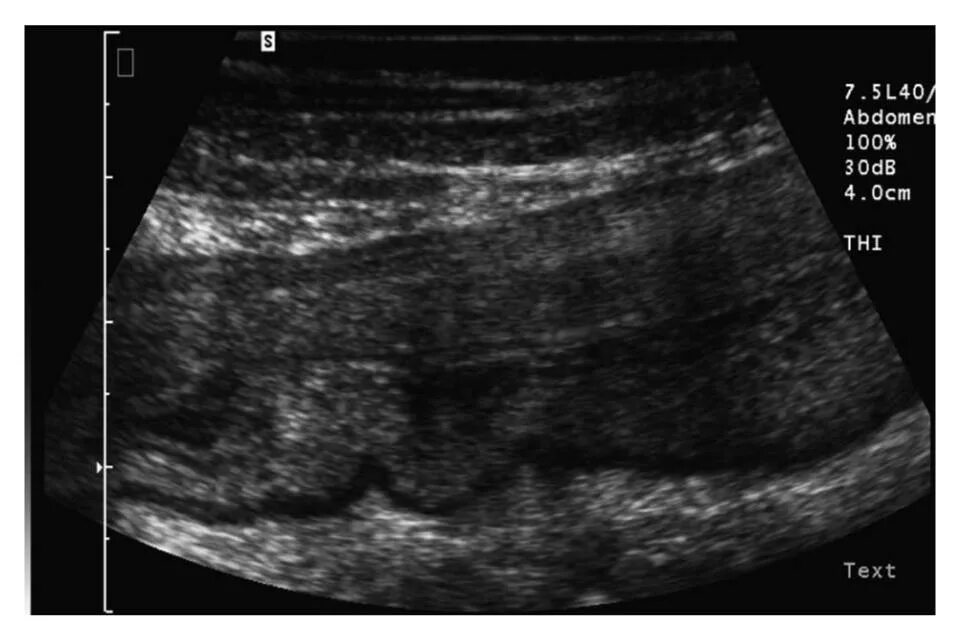

Узи кишечника как подготовиться